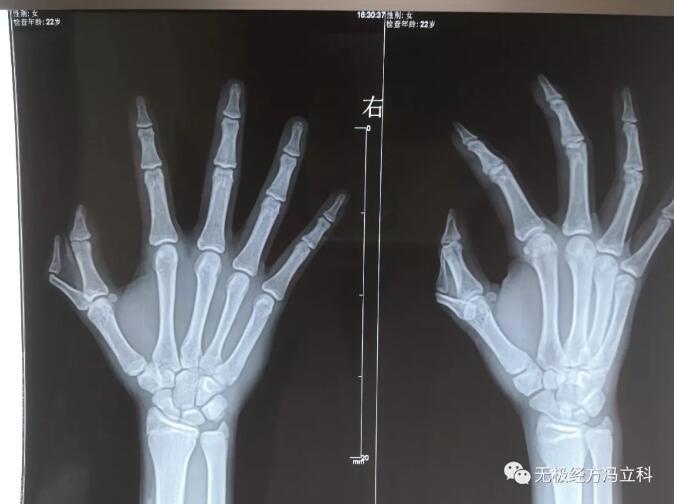

术前患者x光线图.

图片尺寸2667x2000